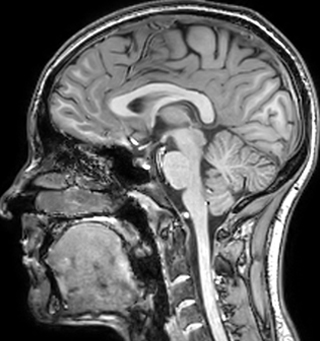

of limiting MWI to the brain, even without the cerebellum, we can now spend about the same amount of time and scan the whole brain and the cervical spinal cord, which is a huge boost for us.” Dr. Rauscher says, “For MWI we perform 3D T2 with 32 or more echoes. This used to take a long time, but with Compressed SENSE we can decrease this to ten minutes for the whole head. Because of the large field of view (FOV) on the readout direction, we even get information from the brainstem, which we previously missed when we were using the GRASE approach. Having the whole head scan is nice because it has spatial resolution, orientation and FOV that are comparable to the standard 3D clinical MS scans, including the FLAIR and 3D T2, and a 3D T1 for brain volume.”

Spinal cord coverage

Smaller, more isotropic voxels

Excellent detail in quantitative maps

Images courtesy of Adam Dvorak, Department of Physics and Astronomy, University of British Columbia

Sagittal 3D FLAIR with 0.3 mm3 voxel volume acquired in 5:12 min. using Compressed SENSE showing a (juxta)cortical MS lesion.